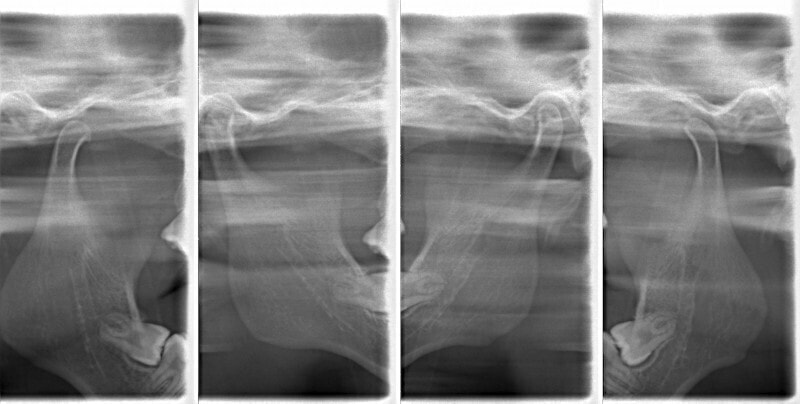

検査時のセファロ分析側貌

上顎劣成長の値が出ています。顔面、下顎骨骨体自体は標準偏差1S.D.内に収まっています。

顔面と顎骨の幅径はある程度確保されているので、非抜歯が可能であると診断しました。

成人の反対咬合なので、少し顎関節にダメージはありますが、重症ではありません。

上顎劣成長症例ですが、鼻腔の状態も悪くありません。

治療後のセファロ分析です。

反対咬合の治療は、FX(フェイシャルアキシス)が開きやすいのですが、治療後も良好な値を保つことができました。FXがあまり開きすぎると、咬合力が落ちてしまいます。

下顎の右側への偏位は解消されました。

特に左側の咬合時の顎関節の位置に改善が認められます。